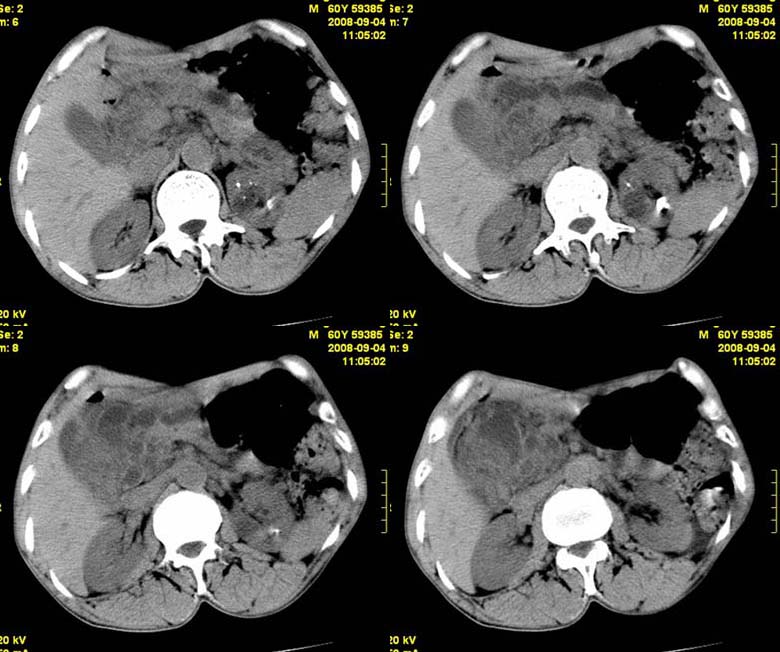

标题: CT15580:M60Y,胰腺病变,平扫+增强 [打印本页]

标题: CT15580:M60Y,胰腺病变,平扫+增强

患者,男, 60,既往有间歇腹痛病史多年,现右上腹痛,加重一月,伴右后背部疼痛,无黄疸,无发热。

胰头区增大,胰管明显扩张,不均匀强化,且与 周围结构不清,后背疼痛,考虑为胰腺头部胰腺癌。

胰头囊腺癌。

胰腺囊腺瘤可能性大,囊腺癌不除外.

同意胰头部囊腺癌。

胰头囊腺癌可能性大。

胰头囊腺癌

结合病史考虑慢性胰腺炎伴脓肿形成。

胰腺囊腺癌/慢性胰腺炎,建议查肿瘤标志物。

胰头囊腺瘤/囊腺癌.

胰腺炎,胰液滞留性假囊肿

考虑胰腺囊腺瘤或慢性胰腺炎。

胰头区增大,胰管明显扩张,不均匀强化,且与 周围结构不清,后背疼痛,考虑为胰腺头部胰腺癌。